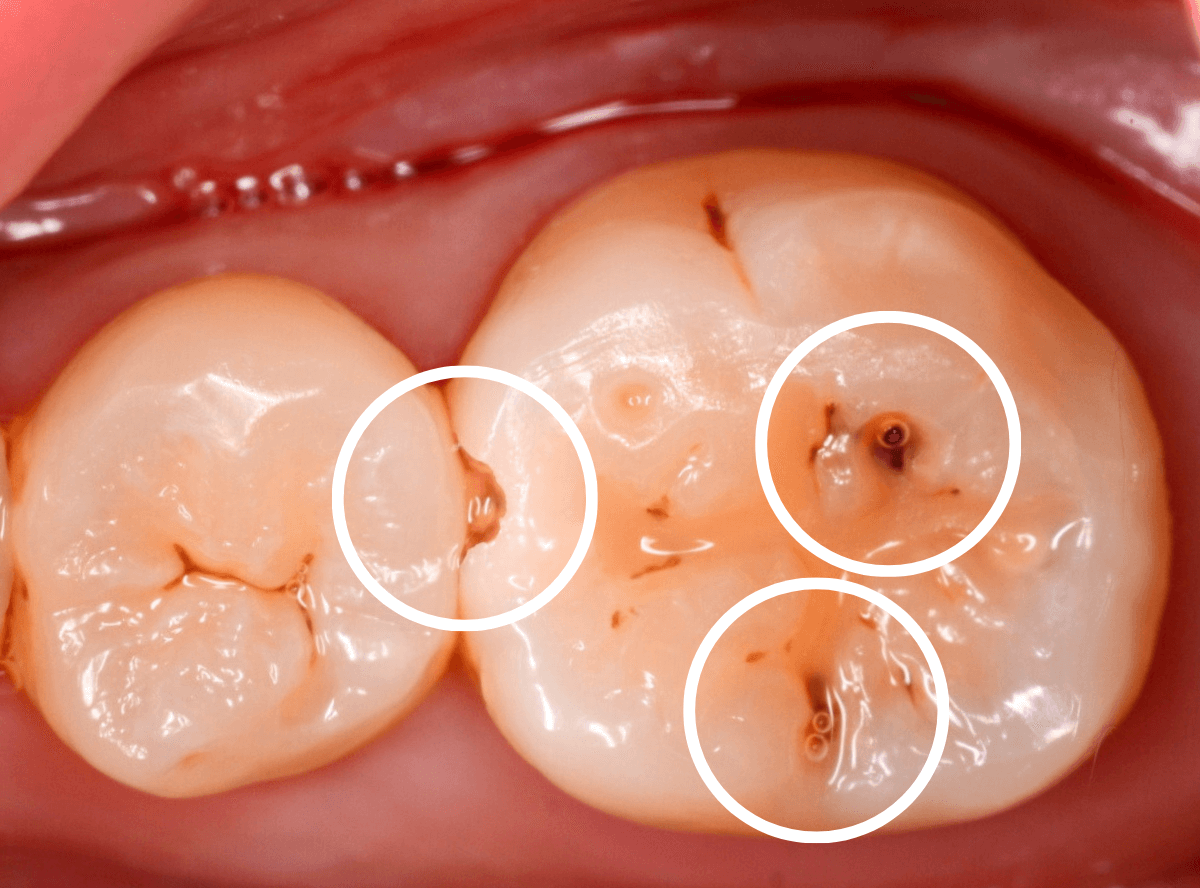

Case.17 4本で6カ所の虫歯

奥歯のスキマが虫歯になっている例です。

この写真でははっきりわかりませんし、患者さんの自覚症状もありません。

レントゲン写真で確認すると、チョコチョコ虫歯になっているのがわかります。

奥歯から治療を開始します。

前後の歯に渡る広い虫歯でした。

手前の歯の虫歯を治療します。

こちらも後ろの歯まで達する広めの虫歯です。

全ての虫歯を除去しました。

歯のスキマが虫歯になると、大抵前後が虫歯になっている事が多いです。

今回は、4本で6カ所が虫歯になっていましたが、自覚症状はありませんので、ご自身で気がつく事もありません。

定期メンテナンスで、虫歯予防・早期発見するようにしましょう。